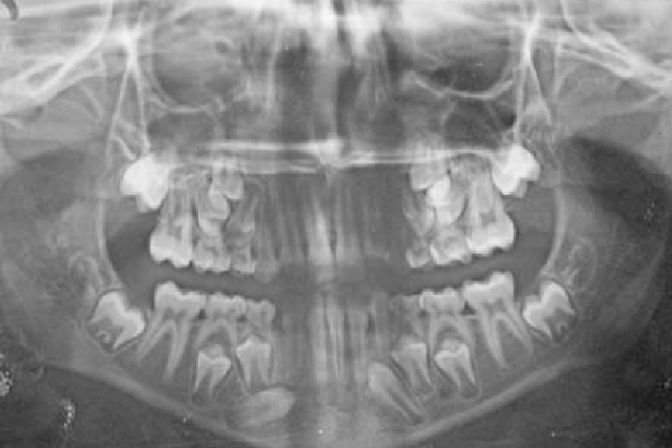

Read MoreDental X-ray

Dental X-rays are pivotal in contemporary dentistry, offering crucial insights into oral health. Leading the way in dental imaging in Delhi is the esteemed RECARVE MAXILLOFACIAL CENTRE & DENTAL STUDIO. Recognized for its proficiency in providing accurate and thorough dental diagnostics, the center plays a key role in advancing oral healthcare.